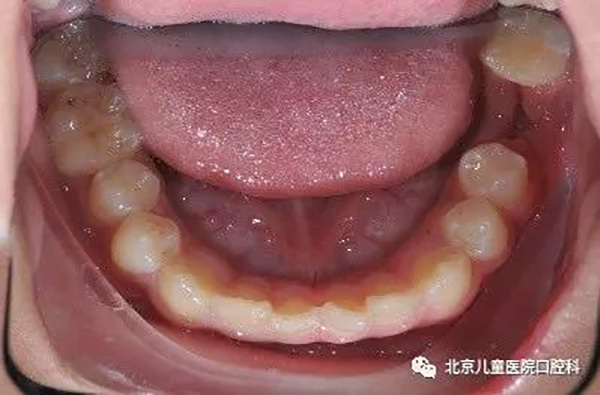

治疗前

治疗中